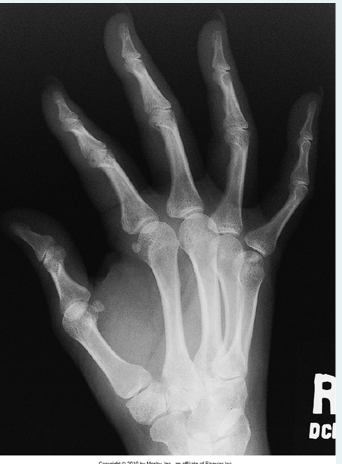

What anatomy indicated the error in this PA oblique hand image?

a.MCP joint spaces are not free of superimposition

b.Space between 4th and 5th metacarpals is too narrow

c.Space between 2nd and 3rd metacarpals is too narrow

d.PIP joint space is not open

A

How well did you know this?

1

Not at all

2

3

4

5

Perfectly

16

Q

Which joint of the hand is formed by the articulation of the head of a metacarpal with a digit?

a.Metacarpophalangeal

b.Carpometacarpal

c.Proximal metacarpophalangeal

d.Distal interphalangeal